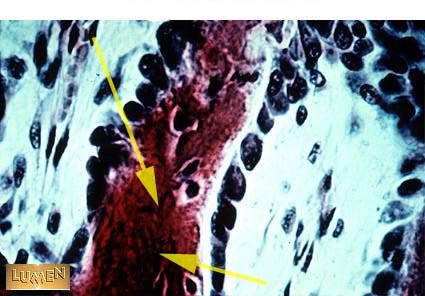

Bony Spicule